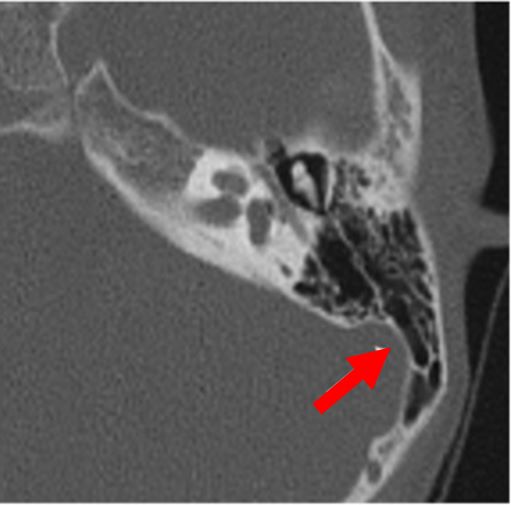

Middle ear deformities

2D CT scan showing deformed middle ear structure

Radiographical features source 8